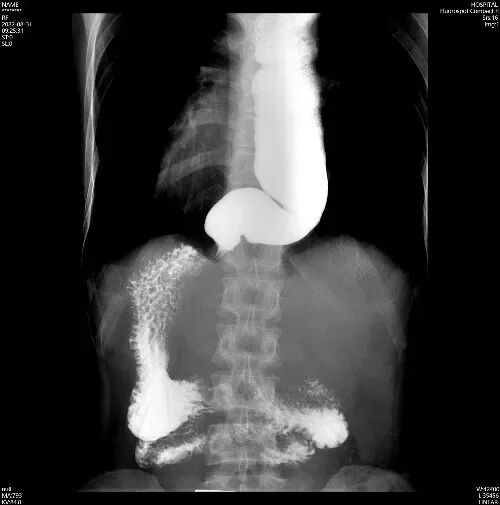

2、食管钡剂造影

给食管拍“动态 X 光”,你需要喝一种白色的钡剂(像牛奶一样的液体),然后在 X 光下观察它通过食管的过程。贲门失弛缓症患者的贲门部位会出现典型的“鸟嘴样”狭窄——食管末端像鸟嘴一样收紧,上面的食管却明显扩张,还能看到钡剂在食管里“慢慢悠悠下不去”。

钡餐造影:食管却明显扩张扭曲,贲门门部位“鸟嘴样”狭窄,钡剂下去慢慢悠悠。